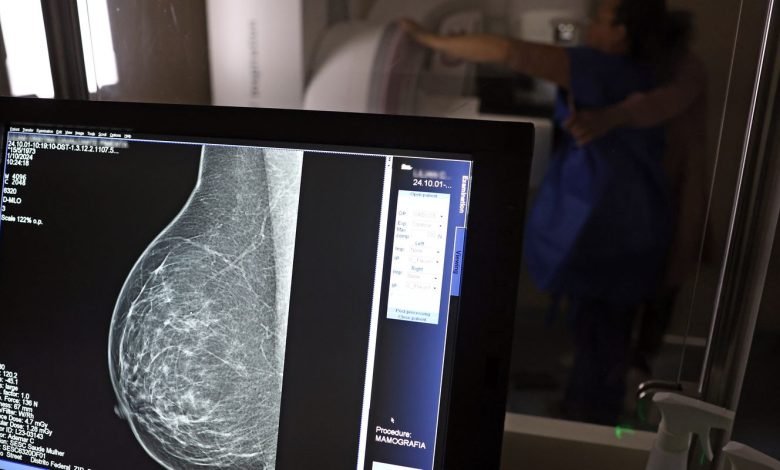

Essas declarações levaram os conselhos regionais de medicina de Minas Gerais e São Paulo a iniciarem investigações contra o médico. O Instituto Nacional do Câncer (Inca), por sua vez, ressaltou que não existem evidências de que a mamografia possa provocar câncer de mama e enfatizou que, ao contrário, o exame é fundamental na prevenção da doença.

Segundo a nota técnica do Ministério da Saúde, é recomendado que mulheres entre 50 e 69 anos, com risco padrão, realizem uma mamografia de rastreamento a cada dois anos, pois esse exame pode auxiliar na detecção precoce do câncer. A AGU ressaltou a importância da conscientização sobre a mamografia para não desestimular as mulheres a fazerem o exame preventivo.